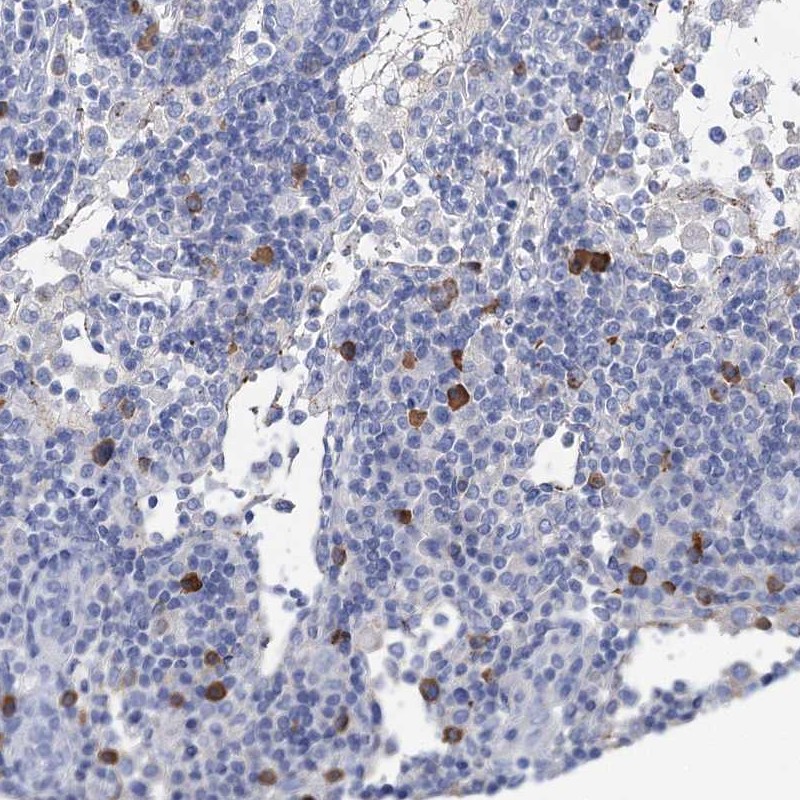

Immunohistochemical staining of human lymph node shows strong cytoplasmic positivity in subset of non germinal center cells.